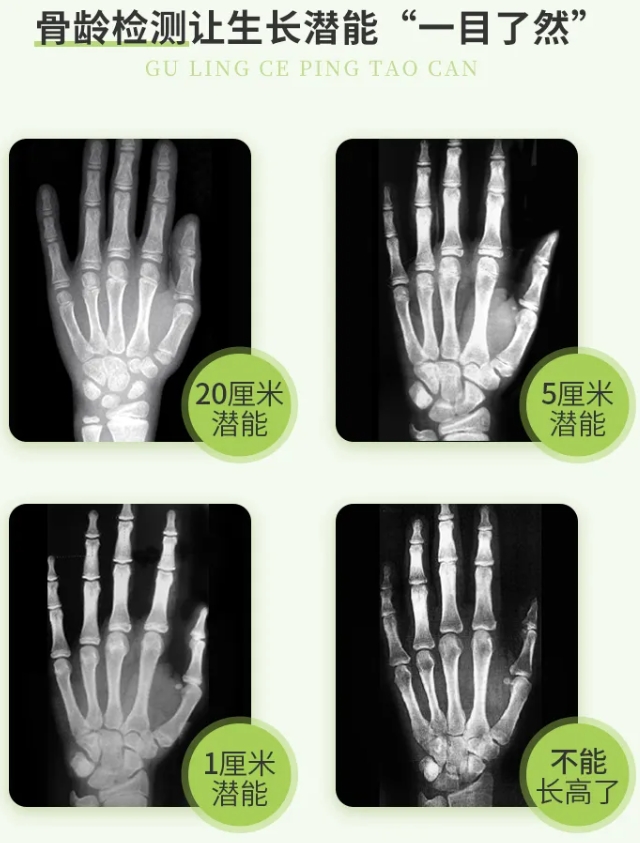

标准骨龄图

身高生长停止的标志是骨骺和骨干完全融合成长板消失,如果想要判断孩子的骨骺线情况,那最清晰的还是带着孩子去拍片,这样我们也能清楚的了解孩子还有多少的生长空间。

骨龄评价方法大致分为3种,包括中华05、TW3、G-P图谱法。因为TW3、G-P图谱法的样本主要来自欧洲和美国的白人儿童,不适用于东亚儿童。2003年-2005年再次进行了中国儿童骨发育调查研究,2006年由国家体育总局正式发布实施的《中国人手腕骨发育标准—中华05》更有参考价值的骨龄报告为AI阅片+医生人工复核。信息包含精确到小数点后1位的骨龄值(如5.3岁或5岁2个月)、骨龄与年龄差值、骨龄身高百分位、根据当前骨龄预测的成年身高、身高百分位、长高潜能评价、检测结果分析和科学指导等。建议大家尽量选择一个固定的、专业的医院,用同一个标准来定期监测骨龄,确保骨龄的增量是准确的,也就是一年或半年骨龄增长了多少。